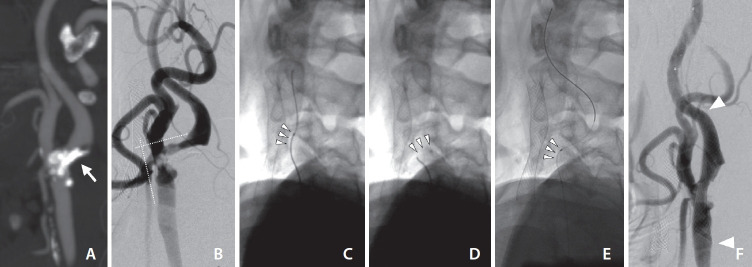

The treatment of carotid stenosis complicated by severe vessel tortuosity can present challenges in distal vessel selection and device delivery. This article reports the use of a steerable microcatheter (SM) for carotid artery stenting (CAS) in such cases. A 67-year-old male with transient lower extremity weakness and bilateral cerebral infarctions was found to have bilateral carotid stenosis. CAS was planned for both carotid arteries due to coronary artery disease. The left carotid artery exhibited severe stenosis with a 90-degree angle between the common and internal carotid artery (ICA). Anticipating difficulty in navigating the device, we used a 2.4 Fr SM. By adjusting the catheter tip to align with the ICA, we successfully guided the wire distally. Following the catheter exchange, a distal protection device was deployed, and CAS was completed successfully. SMs provide exceptional vascular selectivity and support, improving success in complex cases.